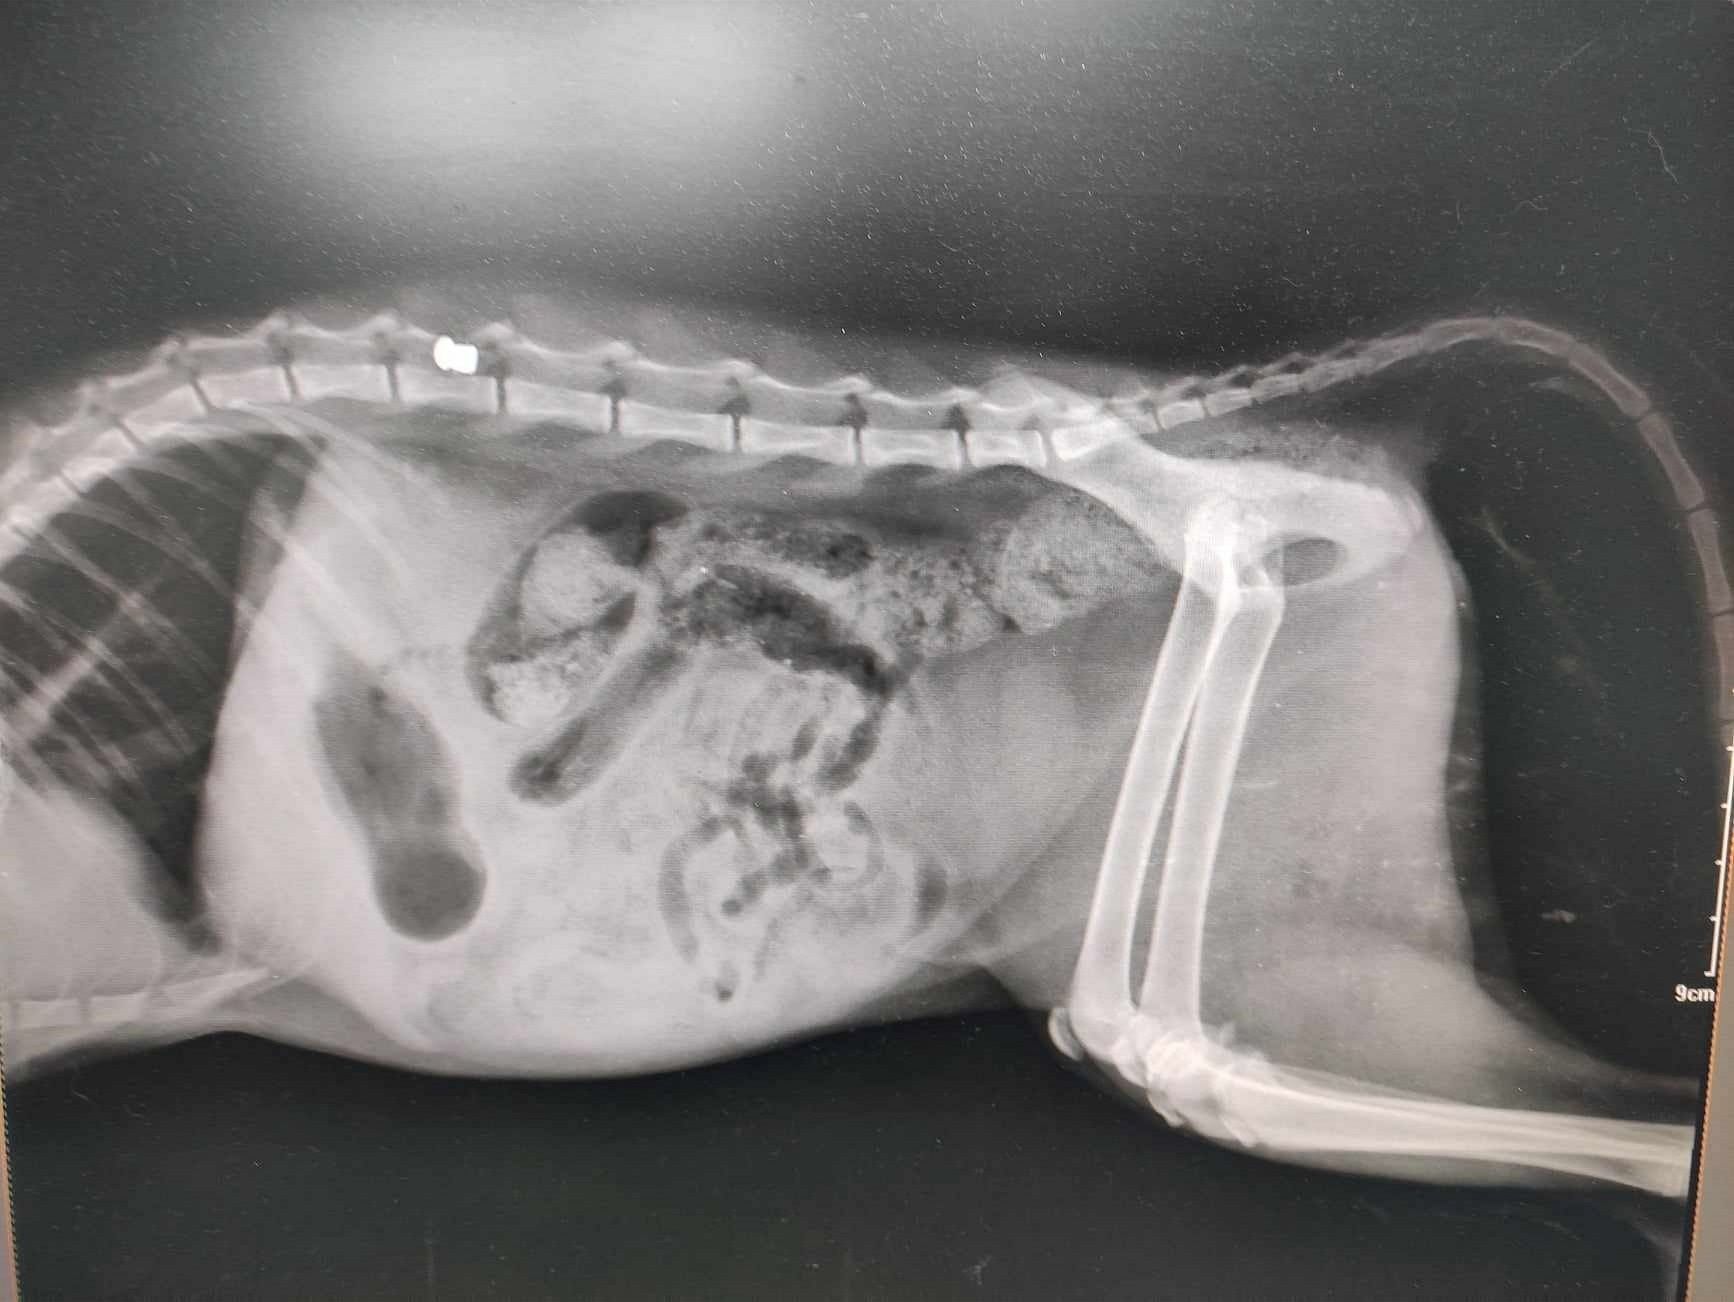

Η ακτινογραφία έδειξε το σφαιρίδιο του αεροβόλο στην σπονδυλική στήλη του ζώου και ίσως η χειρουργική επέμβαση βοηθήσει τη γάτα να ξαναπερπατήσει, εντούτοις χρήματα για αυτό δεν υπάρχουν και απαιτείται να βρεθούν άμεσα ώστε να μην καθηλωθεί ανάπηρο για μια ζωή και αυτό το πλάσμα.

Η γνωμάτευση του κτηνιάτρου.

Η γνωμάτευση του κτηνιάτρου.